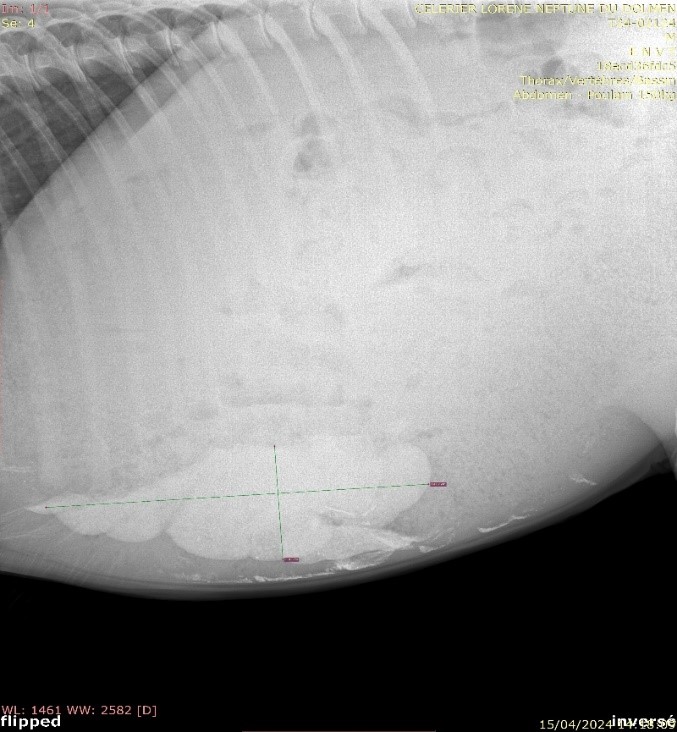

Une radiographie abdominale a révélé une accumulation significative de sable dans le côlon.

Une radiographie de contrôle, réalisée sur place, a confirmé l’évacuation presque complète du sable. Cependant, l’élimination complète du sable restant peut prendre plusieurs mois. Neptune est aujourd’hui un poney en bien meilleure forme, grâce à l’expertise des équipes de l’ENVT et à l’attention bienveillante de ses propriétaires.